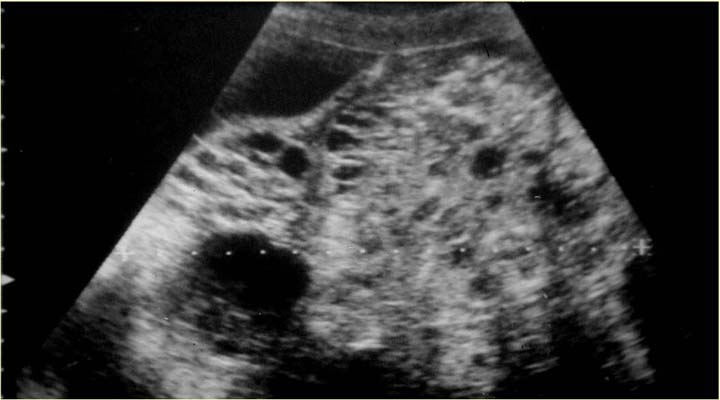

Type III US